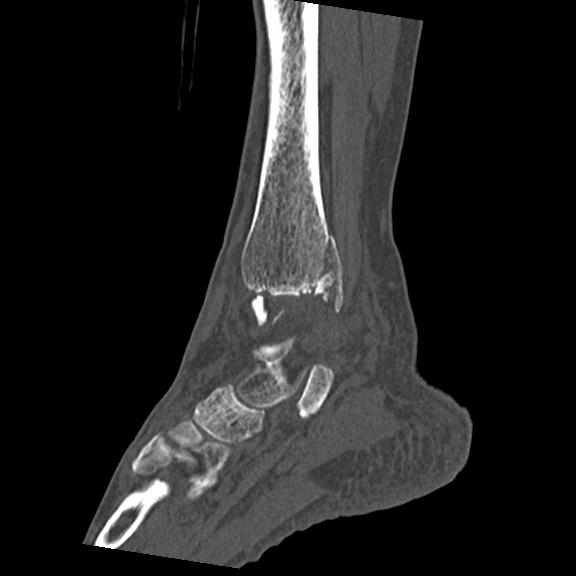

102755 1/4 2R 1/15 2R 右足関節 68歳女性 右三果脱臼骨折